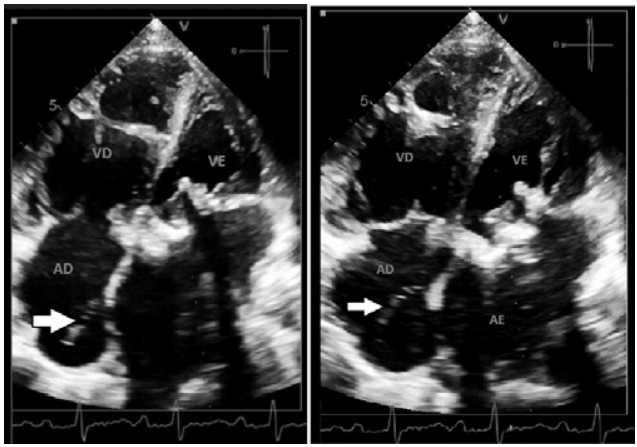

Paciente de 55 anos de idade, sexo feminino, em avaliação da prótese biológica em posição mitral com provável estenose, apresenta uma estrutura móvel em átrio direito (de acordo com a seta).

Com base nessa situação hipotética, assinale a alternativa correta que correlaciona a estrutura apontada pela seta e outro achado que pode estar associado à sua presença.

Imagem: arquivo pessoal.